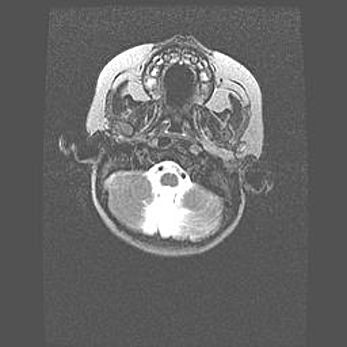

Подострая гематома правой гемисферы мозжечка.

Наружная гидроцефалия.

Возраст: 15 дней

Вес: 3100 г

Пол: женский

Окружность головы: 37 см

Срок гестации: 35-36 недель

При открытой наружной форме гидроцефалии у новорожденных расширяются и переполняются субарахноидные пространства.

Кровоизлияния в мозжечок имеют две клинико-анатомические формы: полушарные гематомы и кровоизлияния в червь.

К появлению этой патологии может привести: повреждения головного мозга, возникающие в результате асфиксии и гипоксии плода при беременности, или травмы во время родов. Редко гематома мозжечка может быть результатом первичной коагулопатии и сосудистой мальформации, диссеминированном внутрисосудистом свертывании, изоиммунной тромбоцитопении.